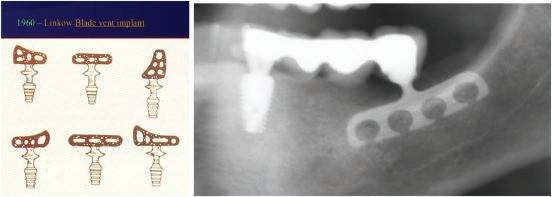

During 1939–60s the concept of the ‘in the bone’ (endosteal) implant arose with the first cylindrical endo-osseous solid screw implant with threads both internally and externally with a smooth gingival collar and healing cap being placed. Following this during the 1940s, a spiral stainless steel post type endosseous implant with a design that allowed bone to grow into the implant emerged and Dahl in Germany, around the same time, introduced the concept of the subperiosteal implant with mucosal inserts (Figure 1.1). This implant was made of cobalt-chromium molybedenum with a direct impression of the struts on the ridge crest taken to construct the denture. Throughout the 1940s–50s variations on the original Dahl design emerged in an attempt to make the provision of implants simpler and included the use of vitallium implants in 1948, the Linkow endoosseous blade vent implant in 1966 with different designs for the maxilla and mandible (Figure 1.2), the ramus frame implant in 1970, made of stainless steel (Figure 1.3) and mandibular transossteal implant which engaged the lower border of the mandible with inserts projecting into the mouth to support a prosthesis (Figure 1.4). The ramus frame and tranossteal implants were predominantly designed for patients with atrophic mandibles who had difficulties wearing dentures and were used to aide denture retention to improve function.

Figure 1.2 Blade vent implants.